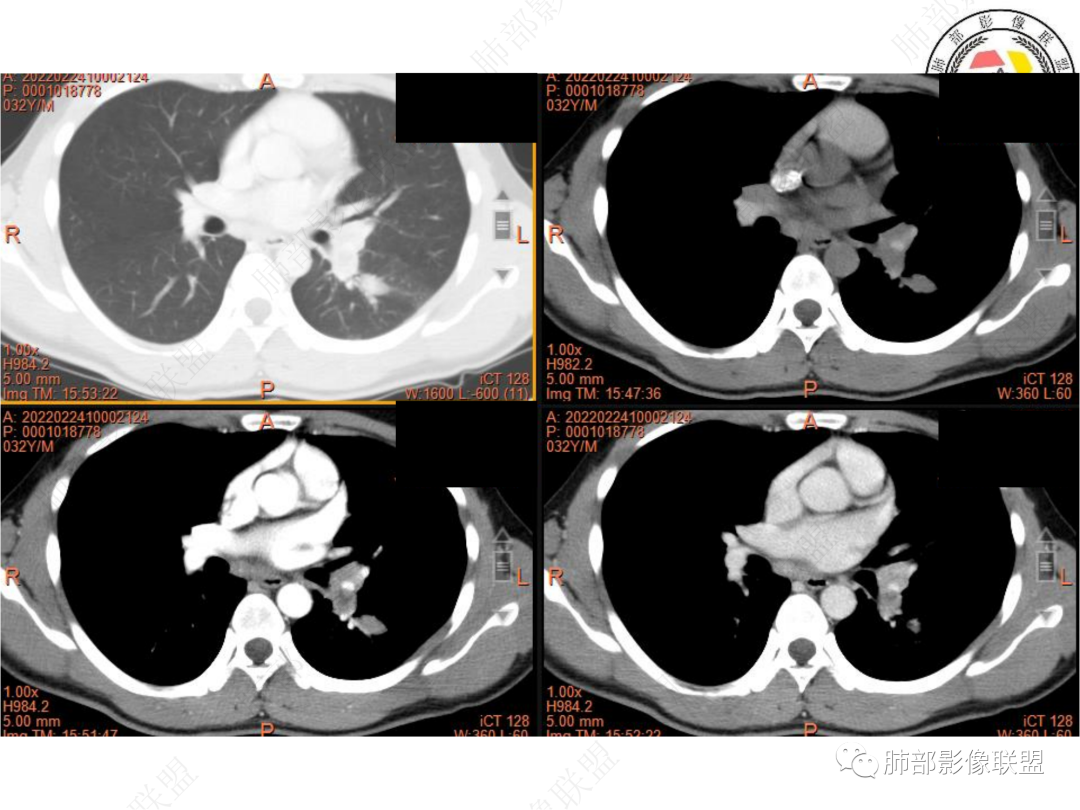

左肺门及纵隔内多发淋巴结肿大,大部分淋巴结显示融合,强化不均匀,内见低密度区,疑液化坏死。纵隔内淋巴结部分周围脂肪间隙不清晰。大血管及左肺主支气管未见受侵改变。

4. 复习文献可知:淋巴结结核的强化特征与其病理改变密切相关,当淋巴结出现干酪样坏死时呈环形强化。有研究认为成人纵隔淋巴结结核具有优势解剖分布部位,在MSCT上淋巴结的密度不均匀比率明显高于纵隔淋巴结转移瘤,增强平衡期以环形强化、分隔样强化、均匀强化为主要表现,并多种强化方式共存。纵隔淋巴结转移瘤可包绕邻近血管,邻近纵隔组织受累及时见强化。然而PET-CT尚且难以区分。

5. 此病例青年男性,纵隔淋巴结环形强化,易先入为主诊断结核。但左肺下叶背段病灶密度均匀,强化明显,整体具备膨隆感,缺少炎性病灶的平直征,病灶周围未见卫星灶,应想到新生物可能。纵隔及左肺门肿大淋巴结,虽有部分淋巴结环形强化特点,但是部分淋巴结周围血管脂肪间隙小时、密度增高,强化明显。至此,亦可与结核的环形强化区分开来。尽管患者年轻,但恶性征象出现时,仍应当高度警惕。